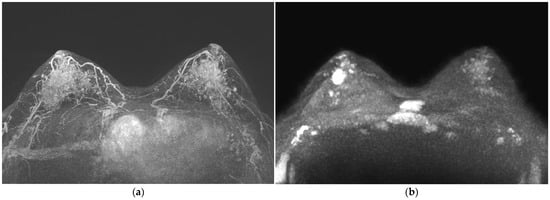

2.3. Image Analysis